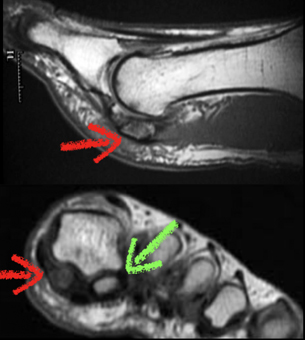

MRI of AVN of the Sesamoid

The Sesamoid should be a white color similar to the other bones (green

arrow)

The sesamoid that is darker is damaged and can lead to AVN (red arrows)

The sesamoid is darker indicating lack of blood flow to the bone.